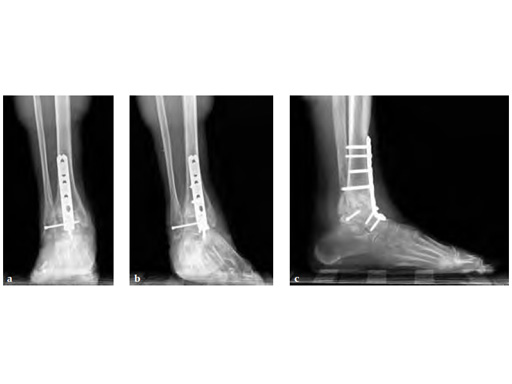

Previous plafond fracture and ORIF through large anterior incision. Increasing pain not relieved by nonoperative preoperative workup revealing deep bony infection. The interim procedure was deep biopsy, curettage and placement of antibiotic self-dissolving beads. Generation IV antibiotics were given. The reimaging showed infection had gone.

Anterior approach through the same anterior incision with placement of anterior plate. Orthogonal screw was added for stability through the fibula into the talar body. Preserving fibula makes it easier for future reconstruction should that be possible (ie, placement of implant in the face of previous infection currently not recommended).